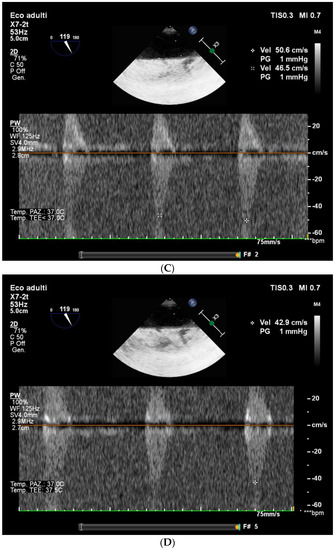

2.2. Case Report 1